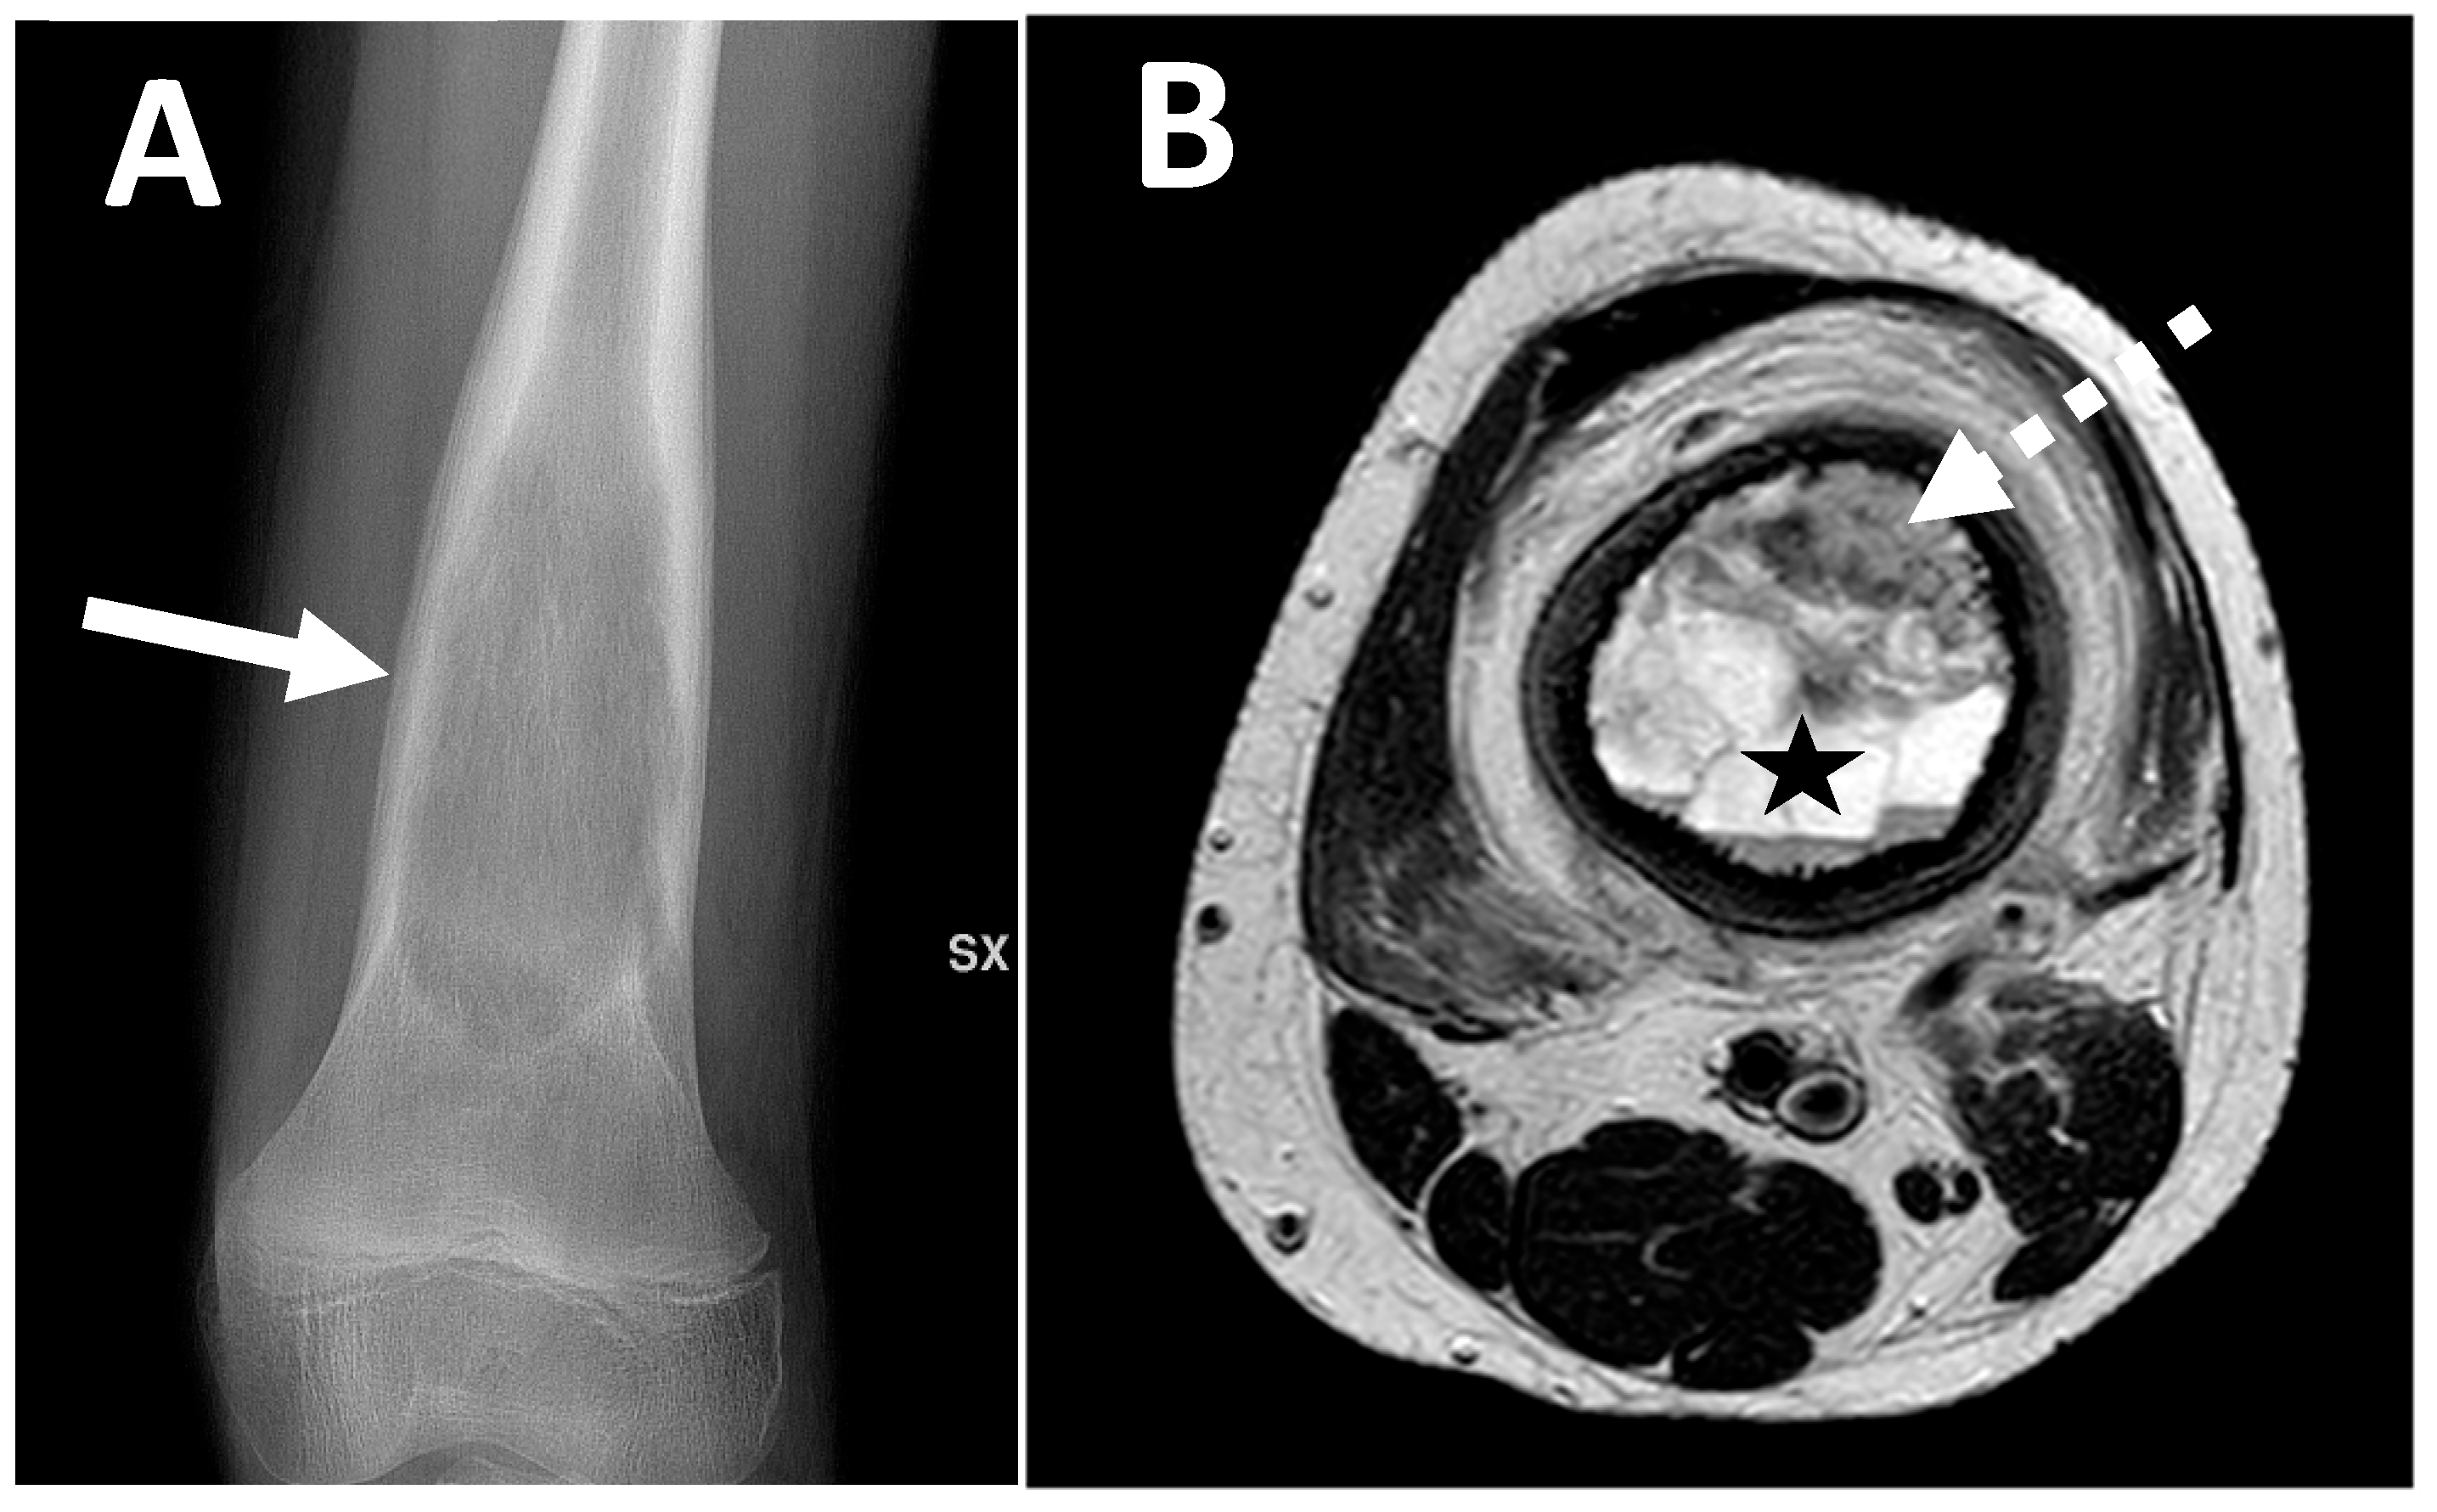

| Conventional osteosarcoma | Mixed (lytic and sclerotic) or completely eburneous | Sunburst, Codman triangle, other irregular/aggressive types | Soft-tissue components frequently displayed |

| Parosteal | Lobulated osseous mass fused with cortical bone, usually with large dimensions, broad implant base | None, non-aggressive ones, or only cortical thickening | Cauliflower-like mass, thin linear cleavage between portions of tumor and cortical bone, frequent intramedullary involvement |